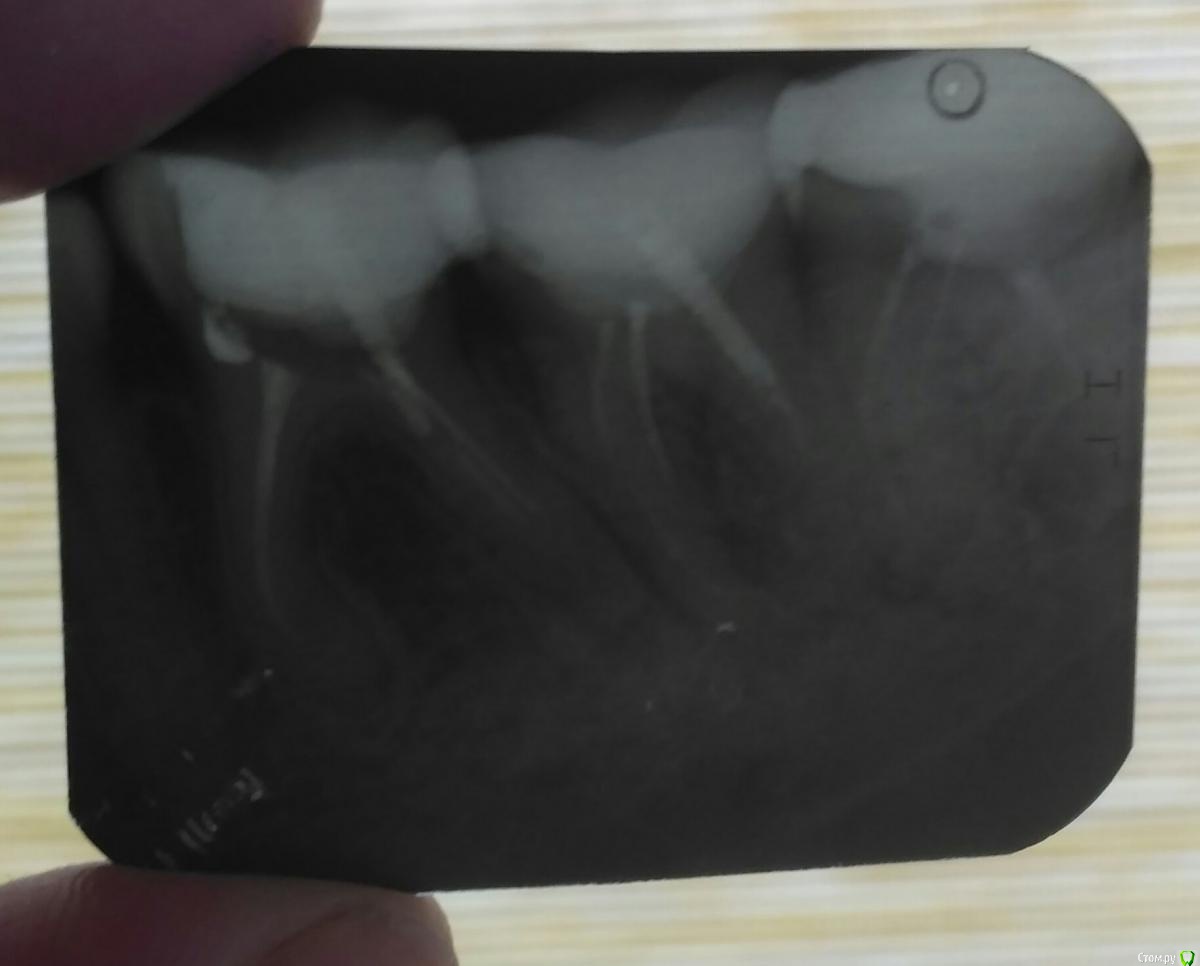

Добрый день!Срочно нужна помощь в данном вопросе Есть ли такая пломба которую нельзя больше снять?Возможно ли хроническое обострение воспалительного процесса после лечения осложненного кариеса? который зуб ранее ,был лечёный и не болел до лечения несколько лет,а просто был отколот?(а после лечения заболел и вызвало осложнения)

может ли вызвать ослабленный иммунитет человека обострение хронического процесса и вызвать агрессивной флорой находящийся  флорой в корневых каналах зубов и периодонтита Возможно ли обострение?

Действительно ли бывает такое что врач не может дойти до каналов и почистить их все если они сильно закупорены?

post-59671-0-72350000-1580303052_thumb.jpg